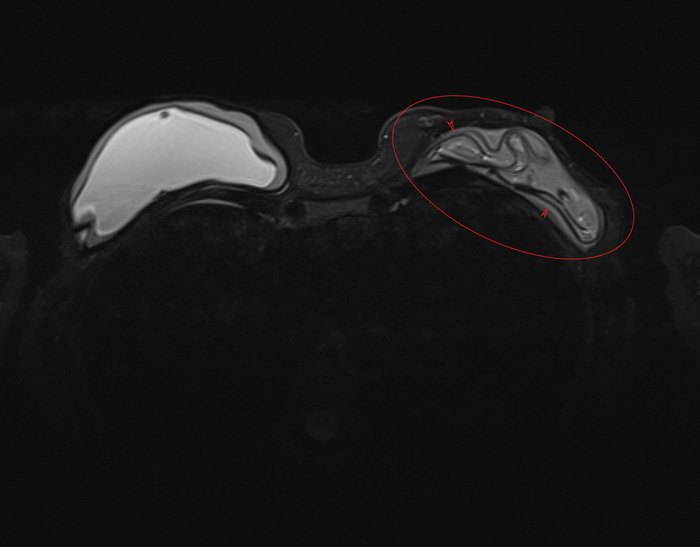

Пациентка, 64 года, перенесла двустороннюю мастэктомию (удаление обеих молочных желёз) по поводу рака 14 лет назад с пластикой с обеих сторон двухкамерные имплантами. Сейчас клинически подозревают фиброз капсулы и возможно разрыв левого импланта. Для подтверждения диагноза провели МРТ молочных желёз (только нативную часть протокола, т.е. без в/в введения контрастного вещества, от которого пациентка отказалась).

Начнём с краткого обзора здорового импланта:

Т2-взвешенное изображение

где центрально расположена камера, заполненная физ.раствором (голубой цвет), на периферии - камера, заполненная силиконом (красный цвет), и отграничено это всё фиброзной капсулой, которой тело старается отграничить инородный объект (пунктирная линия):

если мы сравним правый имплант с левым, то разница очевидна, тут не надо быть рентгенологом, чтобы понять что что-то тут не то, а именно сам имплант меньше, интенсивность сигнала иная (цвет более тёмный) + видны какие-то линии внутри импланта (красные стрелочки):

Линии эти - так называемый признак "лингвини" (или по-английски linguine sign), т.к. похожи они на одноимённую итальянскую пасту лингвини:

и являются ни чем иным как спавшимися стенками камер имплантов, что указывает на внутрикапсульный (в пределах образовашейся фиброзной капсулы) разрыв импланта, но без свободного выхода содержимого в окружающие мягкие ткани.